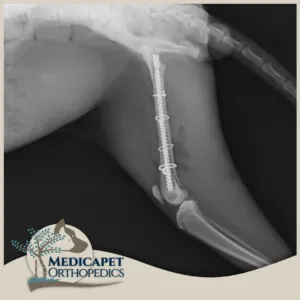

Intrameduller Pin Uygulamaları

“Intrameduller” terimi “kemik içi” anlamına gelmektedir. Bu yöntemde kemiğin medullasına, yani iç kısmına yerleştirilen vidalı ya da vidasız pinlerle kemiği eski pozisyonuna getiriip sabitlemeyi amaçlıyoruz. İntrameduller pin uygulamalarını kemiğin rotasyon ihtimalinin olmadığı durumlarda kullanıyor. Bu ameliyatlarda bazen kemiği dışarıdan da serklaj telleri ile destekliyoruz. İntrameduller pinler iyileşmeyi takiben çıkarılabiliyor ya da iyileşen kemik içerisinde ömür boyu bırakılabiliyor. Fakat büyüme çağında olan hastalarda pinin lokasyonuna göre iyileşmeyi takiben pinin çıkarılmasını öneriyoruz. Ayrıca bazı kompleks kırıklarda intrameduller pinleri plaklarla birlikte de uygulayabiliyoruz.